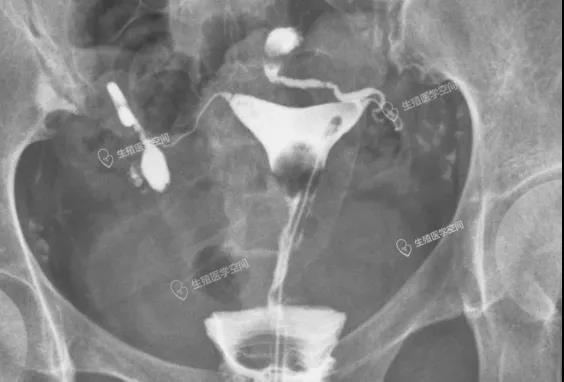

图7:右侧2个基本并联弹簧圈,左侧3个串联部分并联弹簧圈

是一位做了双侧输卵管“致密栓塞”后,做试管婴儿还发生宫外孕。

余X,女,31岁,2020年7月9日在线咨询我,没想到2个月后的2020年9月13日她爱人又在线咨询我说上个月试管移植后出现了宫外孕。